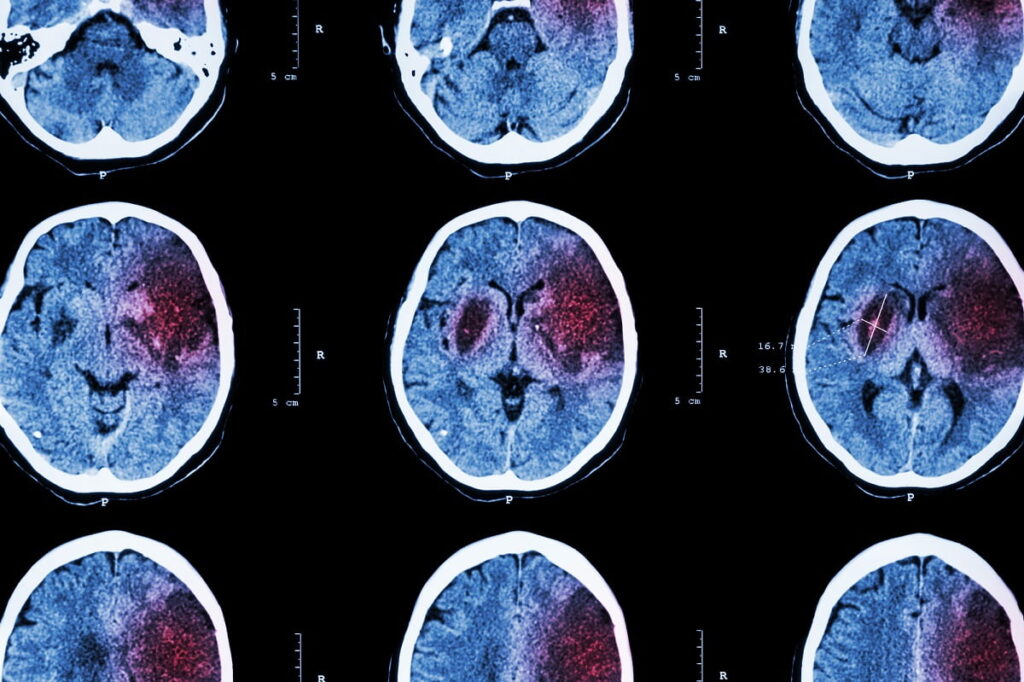

NEW YORK, Sept. 30, 2025 /PRNewswire/ -- Aidoc, the global leader in clinical AI, today announced the U.S. Food and Drug Administration (FDA) has granted Breakthrough Device Designation for the company's novel multi-triage solution that flags a wide array of life-threatening, time-sensitive medical conditions, all within a single workflow. Built on CARE™, the first clinical-grade foundation model in healthcare with FDA cleared solutions, and deployed through Aidoc's aiOS™ platform, the solution is designed to help care teams attend to high–risk cases faster and more consistently across the health system.

This is the first-ever designation for AI with such broad coverage of medical conditions under one solution. The FDA grants Breakthrough Device Designation to technologies that both significantly advance the diagnosis of severe diseases and represent an unmet clinical need. The designation is intended to accelerate access to life-saving innovations by expediting the review process. In this case, it enables parallel review of double-digit indications within a single submission, an important step toward bringing comprehensive, high–accuracy clinical AI to routine care while maintaining robust safety and effectiveness standards.